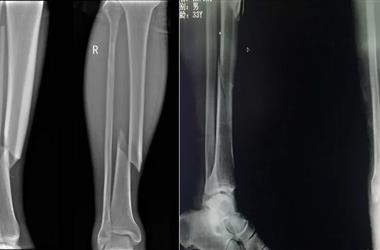

德(de)康醫(yi)療脛骨(gu)骨(gu)折解決方案——脛骨(gu)髓內釘

臨床上對(dui)脛骨骨折患者治療(liao)的非手術(shu)(shu)手段(duan)包括支具、石膏外固定(ding)(ding)與牽引(yin)、手法復位及外固定(ding)(ding)支架的使用等(deng)等(deng);手術(shu)(shu)方式包括鎖定(ding)(ding)鋼(gang)板內(nei)固定(ding)(ding),髓內(nei)釘固定(ding)(ding)等(deng)等(deng)。